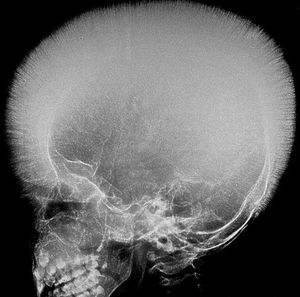

Can you diagnose this Xray! Typical feature of some disease!

Thalassemia.... extramedullary hematopoesis..

Typical end hair appearance in skull, thalassemia! 😎

Hair on end appearance- thalassemia

Hair on end appearance Thalassemia

Crewcut appearance in thalassemia

Thalasemia hair on end